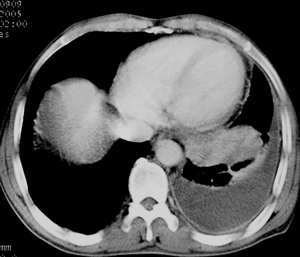

以下是引用jiajie在2005-11-6 22:07:00的发言:[br]1)左肺下叶阻塞性肺炎,胸腔积液,中心型肺癌可能大,建议纤支镜。[br]2)结合30年打石史,双肺弥漫性小结节考虑矽肺。

以下是引用sdqzwyx在2005-11-7 19:59:00的发言:[br]双肺弥漫大小不等的粟粒状结节影;肺纹理走行失去自然,粗细不均,边缘不规则,小叶间隔增厚;左上肺示不规则形致密影,从斑块边缘向周围伸出长短不一的致密索条影,临近的血管、支气管和叶间胸膜等结构受牵拉移位;左下肺示不规则团块状影,其内示空洞,洞内壁尚光整,左侧胸腔积液。右肺下叶背段亦示部分病灶融合。双肺可见局限性肺气肿。[br]诊断:结合病史符合三期矽肺表现(少数矽肺纤维斑块内可以形成空洞,一般认为是斑块中央感染引起坏死所致)但尘肺病人易合并肺结核,诊断可为三期+tb。所以此病人应进一步检查是否合并结核。